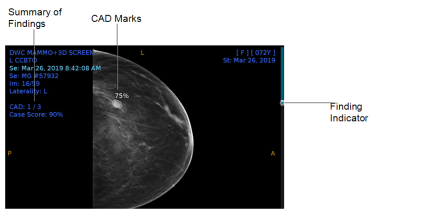

In the following example, which is from the iCAD ProFound AI,one out of the three CAD marks for the exam appears in this image. The Case Score indicates the ProFound AI's confidence, represented as a percentage, that the overall findings identified are malignant. Each CAD mark is circled on the image, with that same percentage of confidence of malignancy, indicated on the mark for that specific finding. If there are multiple findings in the series, each finding will have a finding indicator mark on the scrolling panel on the right side of the image. Not all AI systems will have these exact CAD marks or indicators, so please refer to your AI-specific product documentation for specific details.